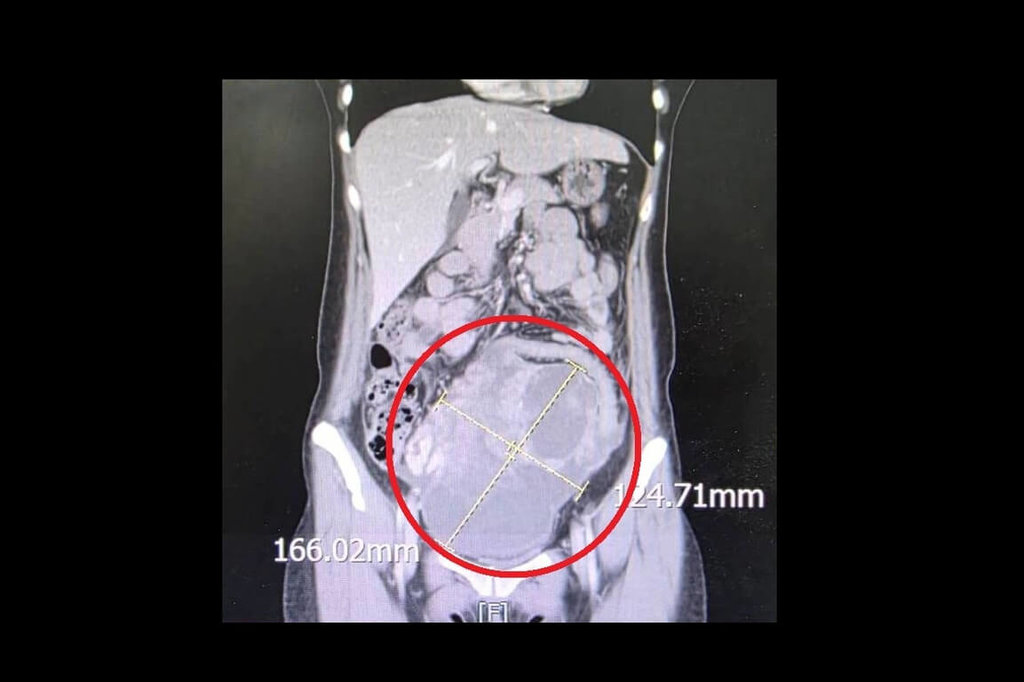

苗栗縣大千綜合醫院婦產科醫師劉榮啟今天分享這起案例,患者為44歲未婚女性,因連續兩週感到腹痛、腹脹且食慾不振,以為單純腸胃問題就醫,意外發現腹部有直徑達16公分的腫瘤,且癌症指數CA-125飆升至900 U/ml(正常值為<35 U/ml)。